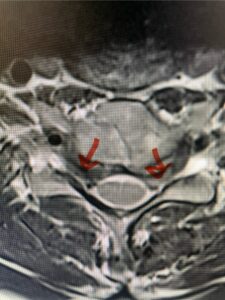

In this next case, this patient is a 47 year-old female who presents with intractable low back pain with severe pain, numbness, and weakness in the right lower extremity that had gotten progressively worse over a year. The patient had failed conservative management including physical therapy and epidurals. She was noted to have ⅘ weakness of plantar flexion. MRI demonstrated a large right L5-S1 disc herniation with severe compression of the descending right S1 nerve root (Fig 3). It was decided to perform a right L5-S1 hemilaminectomy for removal of the disc fragment and decompress the S1 nerve root. When you expose the disc, one must be certain to release any anterior adhesions to the nerve root in order to prevent a dural tear during retraction of the nerve root. It is also important to make sure during exposure and you finally encounter the dura after removing the ligamentum and fat, to make sure you are looking at the nerve root and not the main trunk of the thecal sac because if you don’t you can avulse or damage the nerve root if you retract the wrong structure.

Fig. 3a: Sagittal and axial T2-weighted lumbar MRI images demonstrating large right L5-S1 disc herniation (red arrows)